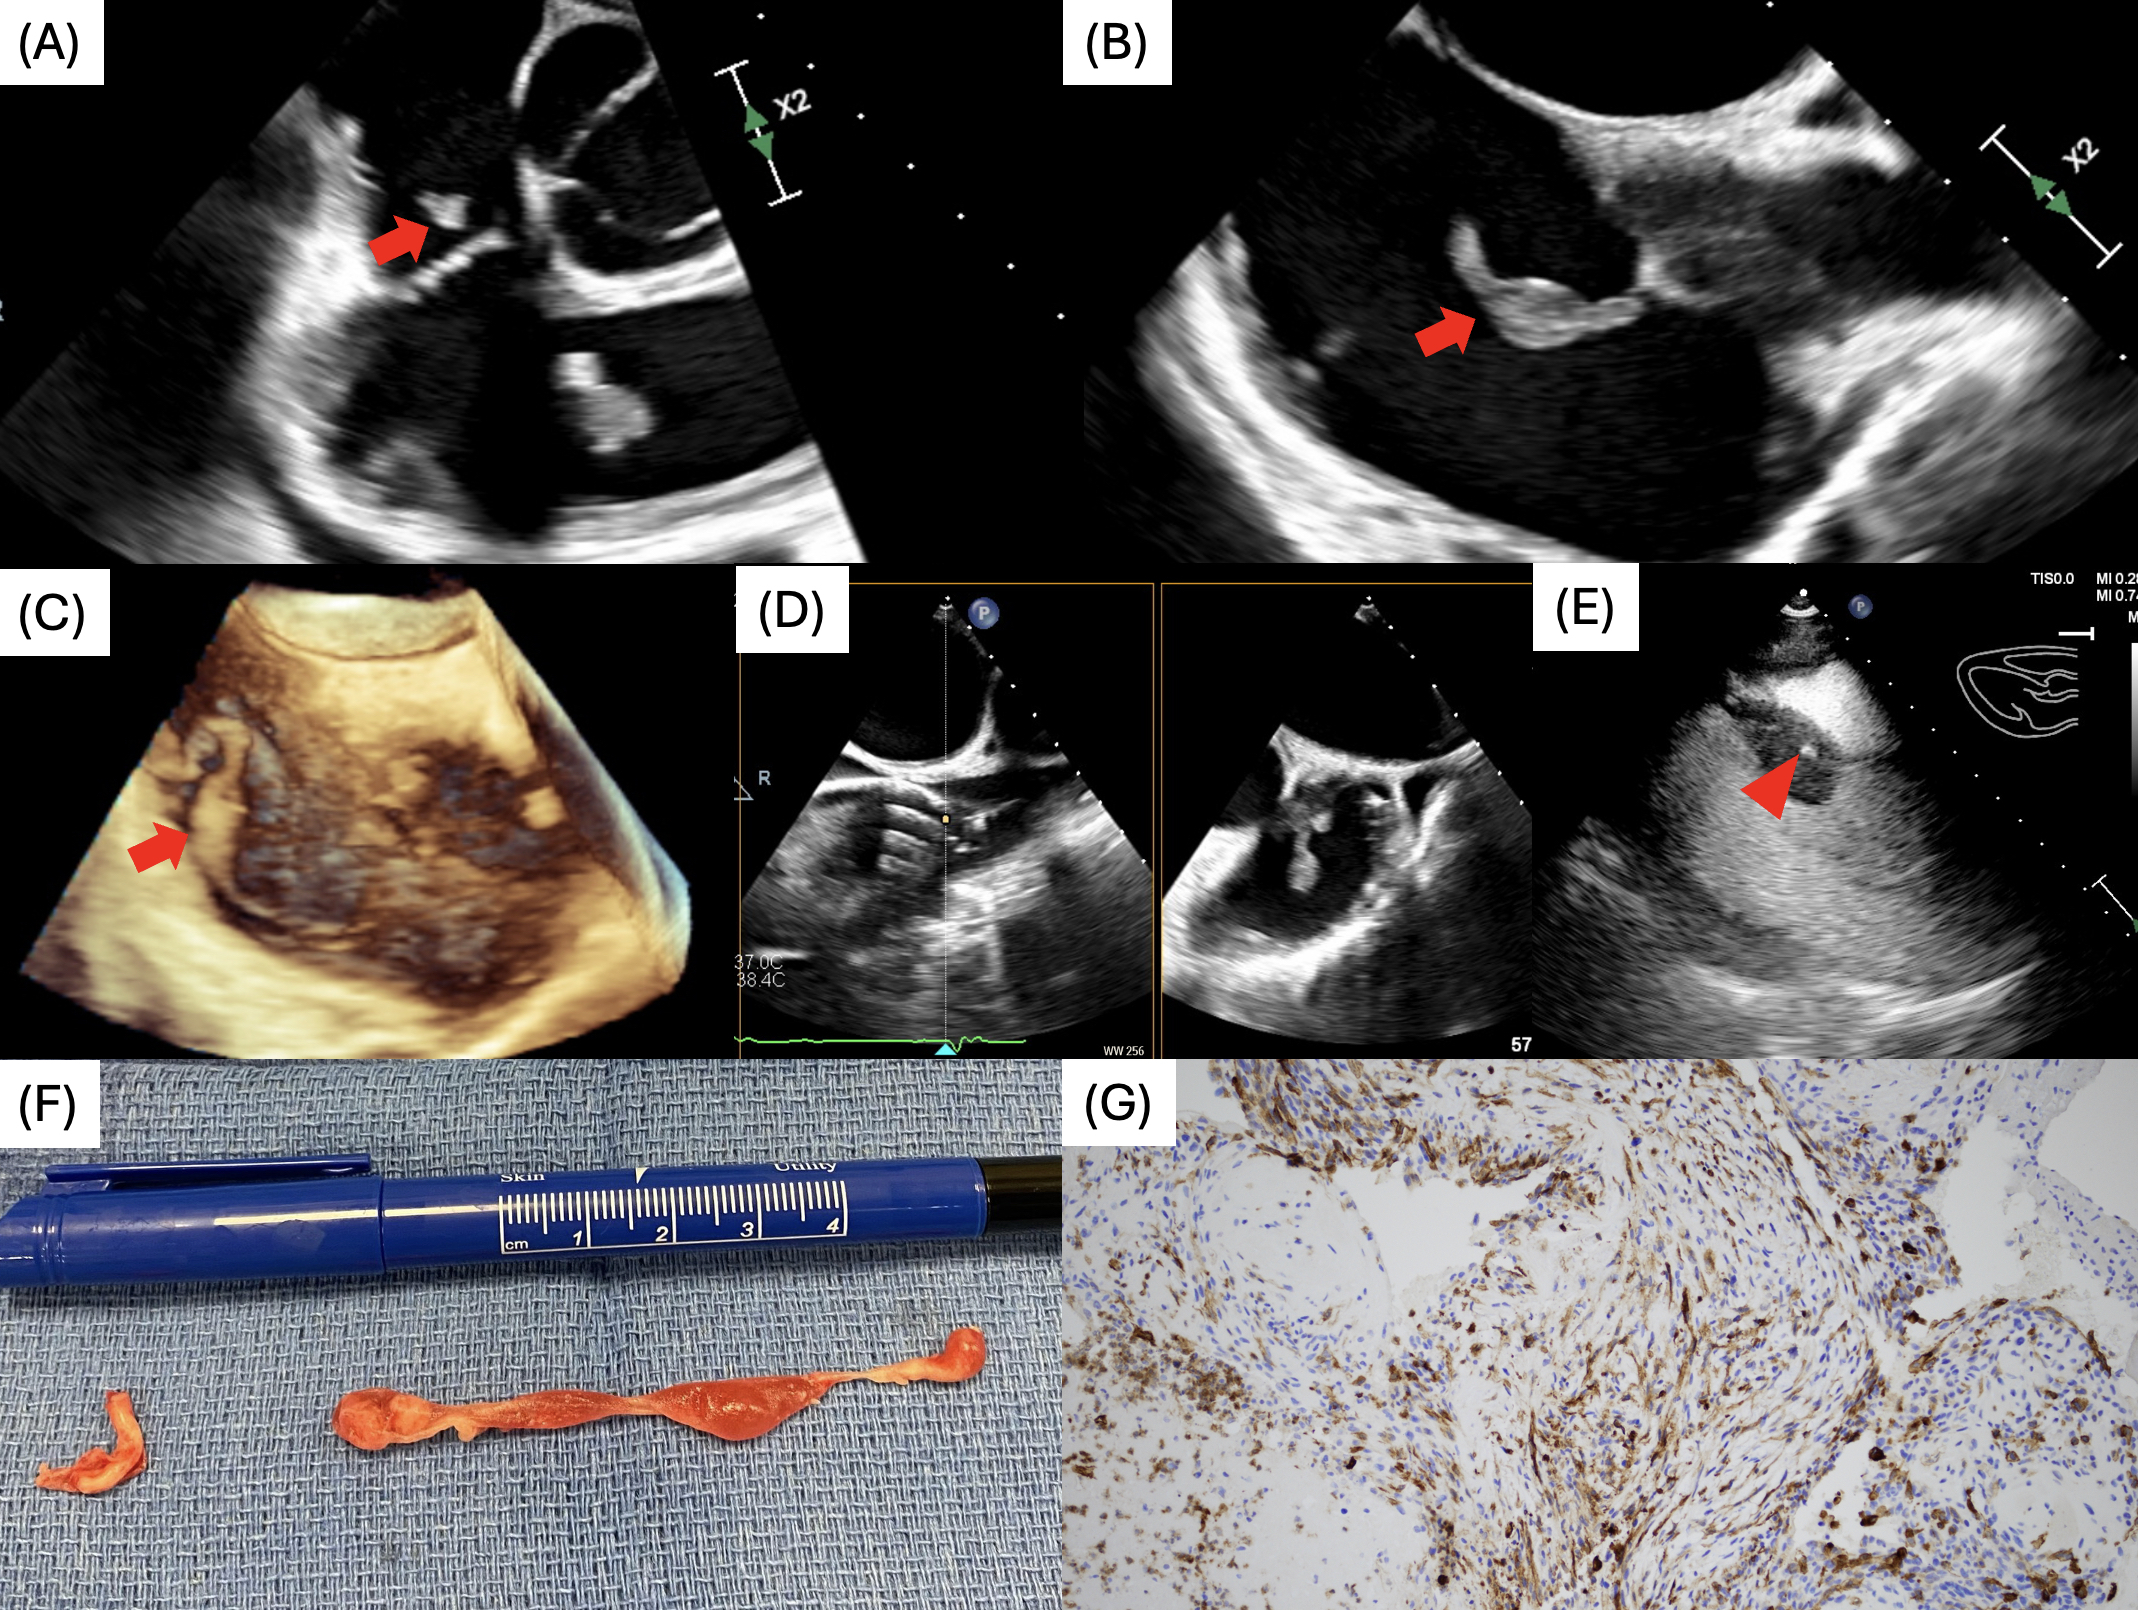

Abstract Body (Do not enter title and authors here): A 66-year-old male presented with 5 months of worsening left flank and lower back pain. Three weeks prior to this presentation, he was seen at an outside facility where he was found to have a left renal mass that was not further worked up. CT Abdomen and Pelvis showed an enhancing heterogenous lesion at the left superior renal pole, left adrenal gland lesion, and a pulmonary artery filling defect. This defect, along with concern for metastasis, led to a CT chest angiogram that reported small left upper and lower lobe pulmonary emboli. A transthoracic echocardiogram (TTE) was ordered and showed a linear highly mobile mass in the right atrium that was intermittently protruding into the right ventricle and into the main pulmonary artery through the pulmonic valve. There was no visible evidence of tumor extension of the renal mass into the inferior vena cava. Based on this, the highest differential was a clot-in-transit. After collaboration with the pulmonary embolism response team and echo team, the patient underwent aspiration thrombectomy via AngioVac system with transesophageal echocardiography (TEE) guidance. Most of the mass was removed, but there was a residual small portion adherent to the superior vena cava that was not amenable to aspiration. Grossly, the removed mass did not have the classic appearance of thrombus. The specimen was sent to pathology and returned as poorly differentiated carcinoma with spindle cell pattern positive for PAX8, CK7, CD10, pancytokeratin, and vimentin concerning for renal cell carcinoma. Post procedural transthoracic echo found to have new basal septal globular mass with vascularity seen on echo contrast imaging concerning for vascular involvement consistent with myocardial metastatic invasion. Cardiac magnetic resonance imaging could have aided in more precise tissue characterization to differentiate between clot or tumor prior to aspiration thrombectomy. This case demonstrates the significance of a detailed history and physical exam, use of multimodality imaging, and multidisciplinary collaboration to manage a rare cardiac condition.